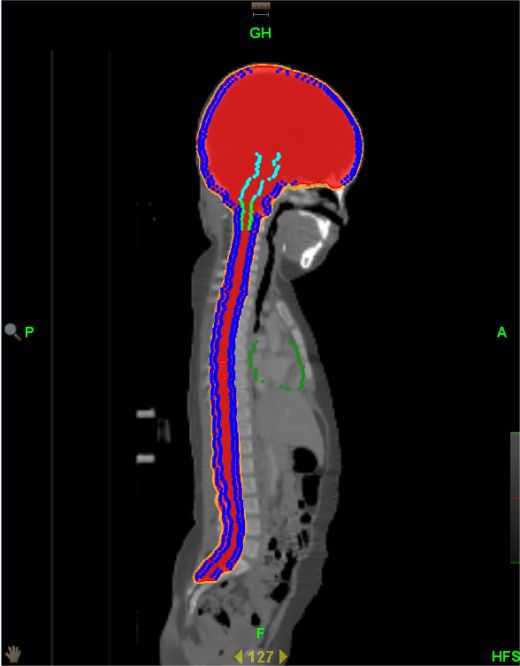

为了让“我”的优点发挥的更加明显,让更多的患者能够在“我”的治疗下得到痊愈。湘南学院附属医院引进的TomoTherapy(简称TOMO)——螺旋断层放疗系统,属于最新一代放射治疗设备。是目前唯一采用放疗照射与CT同源的影像引导放疗系统。成像精度高达±0.1mm,远远高于常规加速器。

与普通的“我”相比,TOMO放疗有以下优势:

1、对全身多发病灶及病变较长的大肿瘤,超出普通加速器治疗所能达到的范围,常规放疗往往不能同时包括,TOMO能够实现连续同时完成照射。包括易通过淋巴转移产生多病灶的恶性肿瘤、全脑全脊髓和全身骨髓调强照射等。